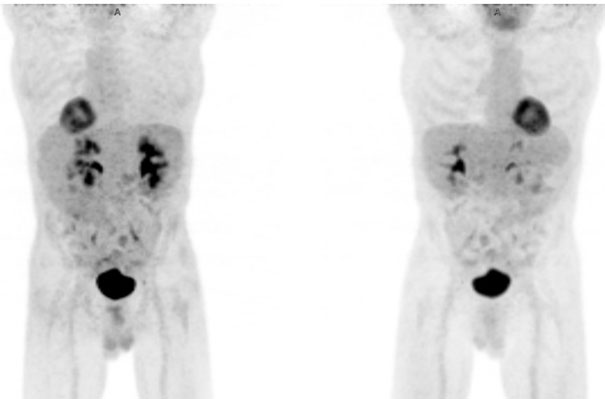

A 65-year-old man with HIV on highly active antiretroviral therapy (HAART) presented with recurrent classical Hodgkin lymphoma (cHL) and visceral crisis. His initial diagnosis was in 2010 when he was treated with 6 cycles of adriamycin, bleomycin, vinblastine, dacarbazine (ABVD) achieving complete remission. The first recurrence was in 2017 when he had extensive lymphadenopathy, splenomegaly, and innumerable osseous lesions. He received 6 cycles of brentuximab, achieving a near-complete remission by April 2018. He subsequently presented in July 2018 with extensive disease relapse, confirmed by excisional lymph node biopsy, and marrow exam documenting 80% replacement of bone marrow by cHL. A PET/CT imaging showed marked progression at multiple sites (Figure 1). At that time, total bilirubin was elevated at 13.3 mg/dL, and alkaline phosphatase of 1142 U/L. His CD4 count was 53 cells/uL. He was treated with nivolumab, receiving only a single dose of 240 mg. However, he was readmitted to the hospital one week later due to significant clinical deterioration, pancytopenia, and progressively worsening liver failure. The total bilirubin escalated to 15.6 mg/dL. He was treated with steroids for possible nivolumab-induced liver injury, and discharged home after a prolonged hospital stay, with hospice care recommended. However, he recovered slowly, without further treatment of HL, and on follow-up after eight weeks he had completely recovered liver function (Table 1). A restaging PET/CT imaging showed a complete response without any evidence of disease (Figure 2). The bone marrow exam was repeated and showed no residual HL. His CD4 count continues to be low at 98 cells/uL, and he is continuing HAART therapy. He is followed closely and the plan is to resume checkpoint inhibitor therapy at disease recurrence.

Figure 2: PET/CT after one dose of checkpoint inhibitor therapy showing no FDG activity confirming a complete remission.